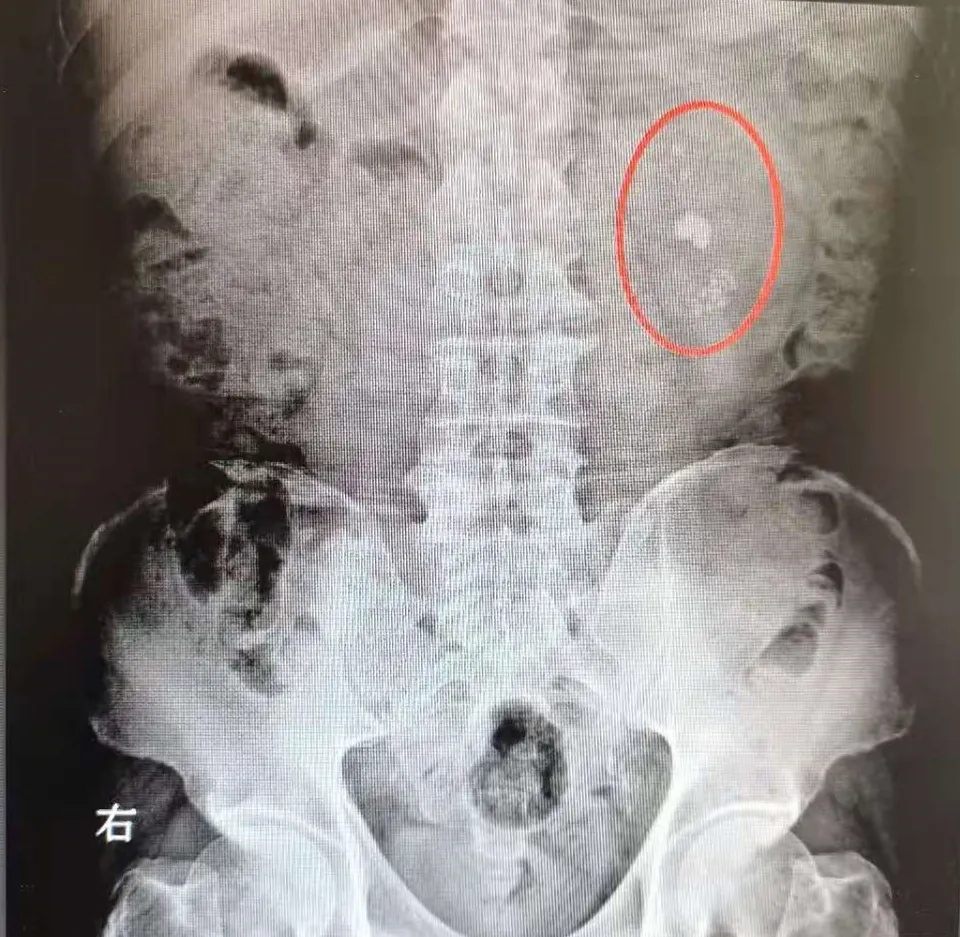

完善相關(guān)檢查,CT示:雙腎結(jié)石、左腎積水、左腎最大結(jié)石直徑約2.4CM;2型糖尿病史10余年。泌尿外科主任李永接診后,針對(duì)患者病情與科室醫(yī)療團(tuán)隊(duì)展開反復(fù)討論,決定為李先生實(shí)施“輸尿管軟鏡下鈥激光碎石取石術(shù)”,此手術(shù)中輸尿管軟鏡具有可隨意彎曲的特點(diǎn),無須在腎臟上‘戳洞’, 完全通過人體自然腔道:尿道、膀胱、輸尿管,直達(dá)病灶進(jìn)行碎石,手術(shù)基本無創(chuàng)傷、無出血,具有創(chuàng)傷小、風(fēng)險(xiǎn)小、恢復(fù)快等優(yōu)點(diǎn)。

術(shù)前X光

鑒于李先生有糖尿病史,必須先控制血糖,否則在手術(shù)及麻醉的影響下,危險(xiǎn)性將大大增加,極易發(fā)生感染。經(jīng)過一段時(shí)間的治療后,李先生的血糖已經(jīng)控制在手術(shù)可行范圍內(nèi)。根據(jù)李先生身體狀況,手術(shù)需要分兩步進(jìn)行,首先為李先生行輸尿管鏡左側(cè)輸尿管雙J管置入術(shù),2周后再行輸尿管軟鏡鈥激光碎石取石術(shù)。李永主任親自操作,歷時(shí)1個(gè)多小時(shí)的手術(shù)非常順利?;颊咝g(shù)后在泌尿外科醫(yī)護(hù)人員的精心護(hù)理下,恢復(fù)狀況極佳,復(fù)查顯示患者結(jié)石已去除,解除了患者多年的頑疾。